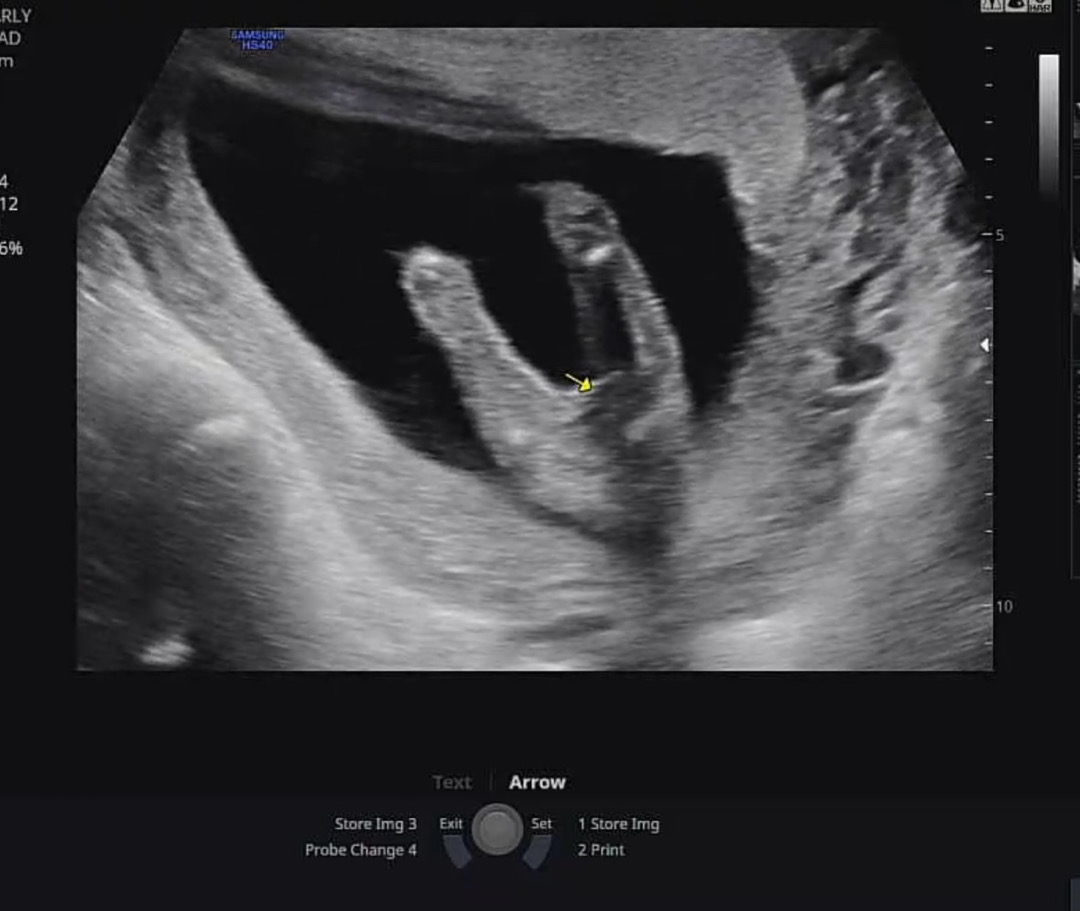

15주 5일 성별공개😚

15주 5일 임산부 독감 주사&A형간염 2차 맞고 왔습니다. (13주 1일에 병원에서 각도법으로 딸 힌트 받았었어요!)성별도 확인했는데.. 13주까지 면 종류가 엄청 땡겨서 아들인가 했는데.. 아들이든 딸이든 좋다고 생각했지만 막상 딸이라고 하니 너어무 기분이 좋습니다😍 이제 상상을 더욱 구체적으로 할 수 있어서 좋네요^^ 오늘도 좋은 하루 보내세요 베동 산모님들🙈😊